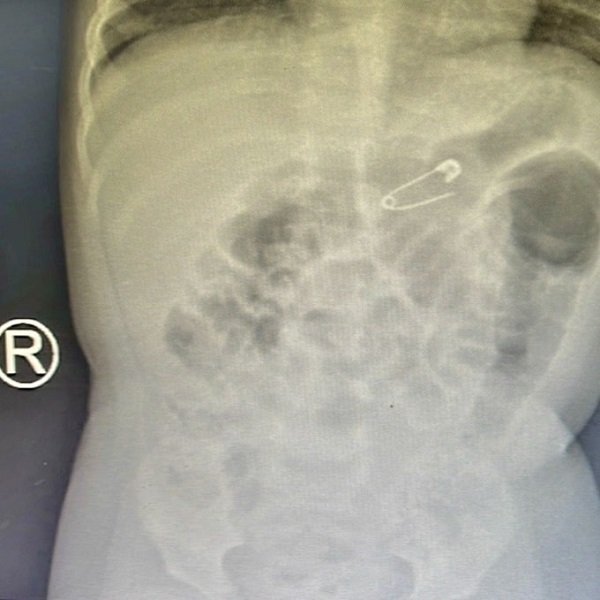

Kết quả chụp X-quang phổi cho thấy dị vật hình kim băng có kích thước 1,5 x 1 cm, mắc kẹt trong vùng bụng của cháu bé.

Hình ảnh dị vật trên phim X-quang. Ảnh: BVCC.